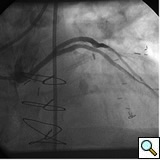

In the past, surgeons used rings to mark the ostia of the vein grafts substantially aiding the angiographer to localize the vein graft ostia during angiography. However, nowadays, it is not a usual practice. The lack of marker can increase the contrast use and radiation particularly in patients without the knowledge of the types and number of vein grafts. As mentioned earlier, right coronary grafts have usually a right sided take off from the aorta. Therefore, using standard view, left anterior oblique (LAO), which is used for right coronary artery catheterization is the view of choice. Left coronary bypass grafts have usually anterior take off. Therefore, a right anterior oblique (RAO) makes it easier to engage the left-sided vein graft ostia preventing foreshortening of the catheter tip. Using RAO, the catheter tip should be oriented to the right side of the screen. The vein grafts to the left system is based on the anatomical proximity of the native coronary to the aorta. Therefore, LAD graft ostia are usually closest grafts to the aortic valve followed by diagonal and circumflex grafts. Circumflex graft ostia usually have the highest take off from the aorta. There are occasional cases with different take off making vein graft angiography difficult. In such a situation, the angiography catheter has to be probed across the aorta in different level in order to engage the ostial vein graft. A non-selective strong contrast injection or aortogram may be necessary to delineate the unusual take off of missing vein grafts or documenting total occlusion of missing vein grafts. Total occluded vein grafts usually have a residual knob in the aorta that can be seen during angiography.

The most commonly used catheters for left heart catheterization and vein graft angiography can be seen in Figure 1 and Figure 4-13. Most of the vein grafts have horizontal take off and can be successfully engaged using a commonly used Judkins right number 4 (JR4) catheter. The JR4 catheter is the most commonly used catheter for the engagement of the right coronary ostium with horizontal take off. However, many vein grafts have unusual take off requiring different catheters. Many right coronary vein grafts have steep inferior take off making the ostial engagement with JR4 difficult or impossible (Figure 10). In such a scenario, a multipurpose catheter which has a shallow angulation is the best choice (Figure 11). The second major challenge in engaging vein graft ostia, particularly vein grafts supplying the left coronary arteries, is the shape of the aorta. A large aorta can make it very difficult for the JR4 catheter to reach the ostial vein grafts. In such a situation, Amplatz (AR) right and left (AL) catheters can be very helpful to reach the vein graft ostia. Amplatz catheters have a larger primary curve and have been used successfully in unusual superior take off of left coronary arteries or vein grafts and in large aorta. Amplatz catheters are available in different sizes (from smaller to larger curve: AR 1, AR2, AL2, AL2 and AL3). Occasionally, a very superior take off of a vein graft requires specially designed bypass graft catheters. Amplatz catheters are also extremely helpful in engaging native right coronary ostium with anterior take off.